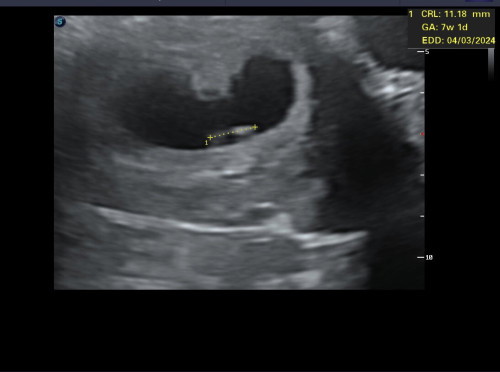

Scan 8weeks, dah nampak heartbeat. Normal tak scan janin usia 8weeks mcm ni?

Saya scan utk 8weeks, janin saiz 7w1d. Sonographer tak cakap apa, scan pastu bg gambar. Tu je. Nak tanya doktor tapi masa tu doktor tak ada, sonographer je. Saya ni ada history jantung baby slow. Scan masa 8 week doktor kata jantung baby slow, tapi scan 8w nmpk ok.